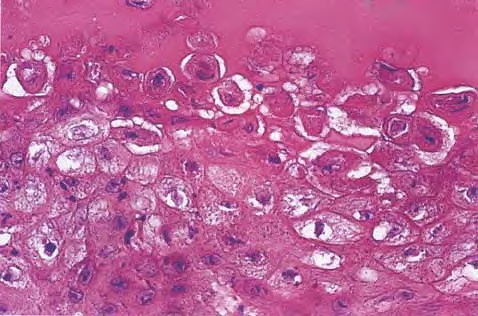

Orf = الاورف